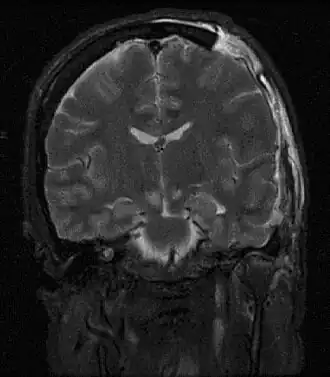

En médecine, on parle d'engagement cérébral lorsqu'il y a déplacement d'une structure cérébrale au travers d'un orifice naturel.

Il existe trois types d'engagement cérébral :

Engagement sous-falcoriel

L'engagement sous-falcoriel correspond au glissement d'un hémisphère cérébral sous la faux du cerveau. Celui-ci est asymptomatique et résulte souvent du refoulement d'un hémisphère par un œdème.

Engagement transtentoriel

L'engagement transtentoriel fait suite au déplacement d'un lobe temporal sous la tente du cervelet. Il se manifeste par une mydriase paralytique unilatérale. Il s'agit alors d'une urgence thérapeutique du fait de la compression du tronc cérébral qui le complique, mettant en jeu le pronostic vital du patient.

Engagement amygdalien

L'engagement amygdalien est le glissement des tonsilles cérébelleuses (anciennement amygdales) dans le foramen magnum (ou trou occipital) et entraîne également une compression du tronc cérébral. Il se manifeste typiquement par des céphalées, des cervicalgies et des crises en opisthotonos. Il peut compliquer une malformation d'Arnold-Chiari.

Engagement diencéphalique

L'engagement diencéphalique secondaire à la pression sur les thalamus de façon bilatérale, il se manifeste cliniquement surtout par un hoquet, et des troubles de vigilance.